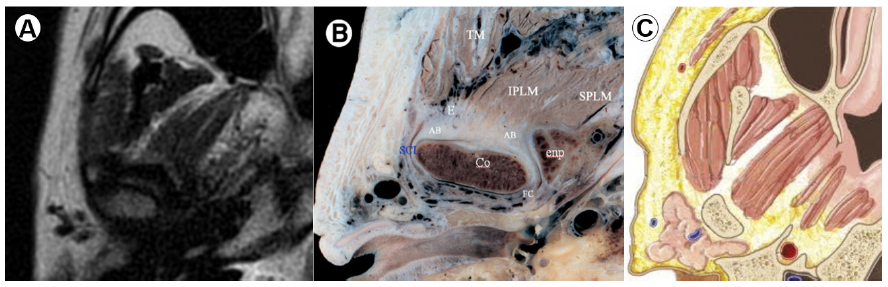

En la figura 4 presentamos cortes sagitales a nivel de la parte media del disco articular con tres imágenes diferentes, a la derecha un esquema anatómico, al medio un esquema de espécimen, y a la izquierda la respectiva imagen de RM al mismo nivel de corte; en estas tres imágenes podemos observar estructuras anatómicas de relevancia como: el músculo temporal (TM), el cual se inserta en la apófisis coronoides (la cual se evidencia como un área hipointensa por ser muy inorgánica – corticalizada –), el vientre inferior del músculo pterigoideo externo (IPLM) él se inserta en la fosa pterigoidea (cuello del cóndilo mandibular), así como la eminencia articular (banda hipointensa en forma de media luna convexa hacia abajo), el cóndilo mandibular donde podemos evidenciar su cortical (banda hipointensa que la circunde), y dentro de la cortical sobre el espacio medular (región isodensa del cortical hipointensa). Por último, se evidencia la banda anterior (AB) y posterior (PB) del disco, configurando los extremos de la misma (figura 4)

En la figura 5 presentamos imágenes a un nivel de corte parasagital medial con respecto a las imágenes de la Figura 4, donde además de evidenciarse las estructuras anteriormente mencionadas en la figura anterior, también podemos evidenciar al vientre superior del músculo pterigoideo externo (SPLM), el cual se inserta en el borde anterior de la capsula y disco articular (figura 5).

A: RM en T1 corte parasagital (TM) Músculotemporal, (IPLM) Vientre inferior del músculo pterigoideo externo, (E) Eminencia articular, (Co) Cóndilo mandibular, (AB) Banda anterior, (PB) Bando posterior. Tomado de: Alomar et al., (15). B:Espécimen en parasagital. Tomado de: Alomar et al., (15). C: Ilustración en plano sagital. Modificado de: Gray’s Anatomy The Anatomical Basis of Clinical Practice., (14).

A: RM en T1 cortesagital (TM) Músculo temporal, (SPLM) Vientre superior del músculo pterigoideo externo, (IPLM)Vientre inferior del músculo pterigoideo externo, (E) Eminencia articular, (AB) Banda anterior, (PB) Banda posterior (Co) Cóndilo mandibular. Tomado de: Alomar et al., (15). B: Espécimen en parasagital. Tomado de: Alomar et al., (15). C: Ilustración en plano sagital. Modificado de: Moore Clinically Oriented Anatomy., (10).